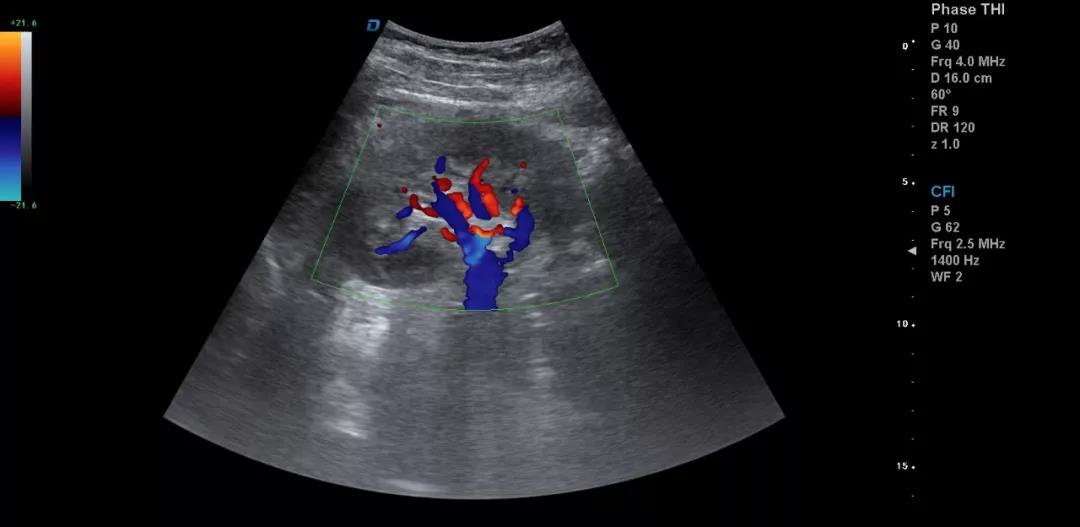

一個正確的診斷往往是醫(yī)學理論、臨床經(jīng)驗和正確思維方法三者有機結合的結果。醫(yī)用B超機作為一種常見的檢查儀器,對某些疾病的診斷具有明顯優(yōu)勢,已成為一種便捷、無創(chuàng)、有效的檢查手段。因此,超聲診斷的目標就是減少漏診、誤診,或為最終診斷提供更多更有價值的信息。

典型圖片、經(jīng)典病例圖片、動態(tài)影像資料積累的多了分析總結之后就提高了。疑難病例資料積累后,可以隨訪病人,然后總結得到的臨床資料和病理結果。

有了手術結果和病理才會有真正的提高。按器官、按系統(tǒng)、按學科進行總結每一個、每一類疾病正常及異常圖片就是知識的積累。